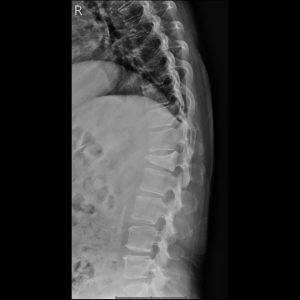

T-spine A-P view

T-spine Lateral view